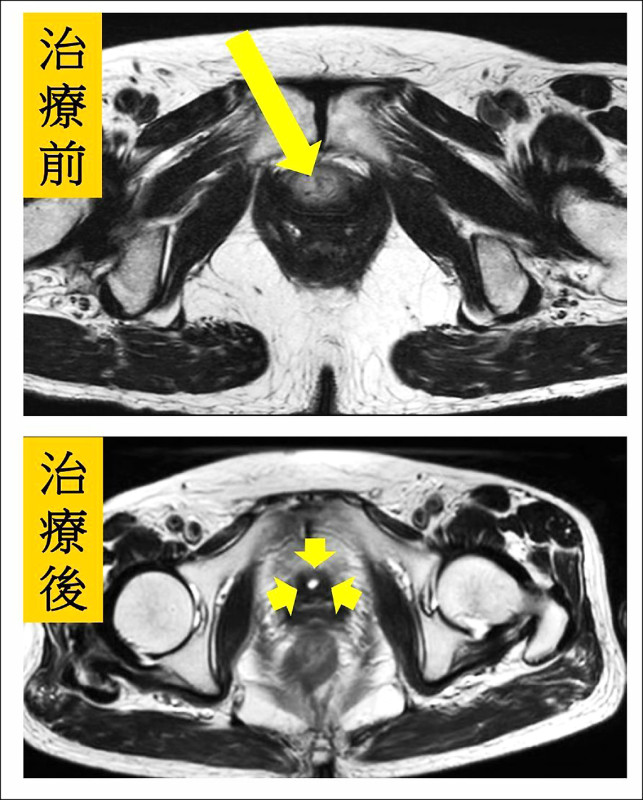

70多歲的李姓婦人因長期性反覆小便疼痛、血尿及解尿困難到泌尿科求診,經安排內視鏡檢查,發現尿道完全被腫瘤阻塞,經施作內視鏡尿道腫瘤刮除,術後病理報告為罕見HPV(人類乳突病毒)導致的尿道鱗狀細胞癌,後續結合血液腫瘤科、放射腫瘤科安排化療和放射治療,經3個月治療後追蹤,發現尿道腫瘤已消失,目前仍追蹤治療中。

放射腫瘤科主任盧皓維表示,患者腫瘤侵犯範圍廣泛,若直接進行手術切除,恐將影響正常泌尿道功能,決定會同血液腫瘤科規劃治療策略,爭取泌尿道器官保存的可能性。經跨科團隊充分討論後,最終決定採取根治性同步化學放射治療,以尿道腫瘤作為主要照射目標,患者結束療程後追蹤檢查顯示腫瘤已消失,治療成效良好。